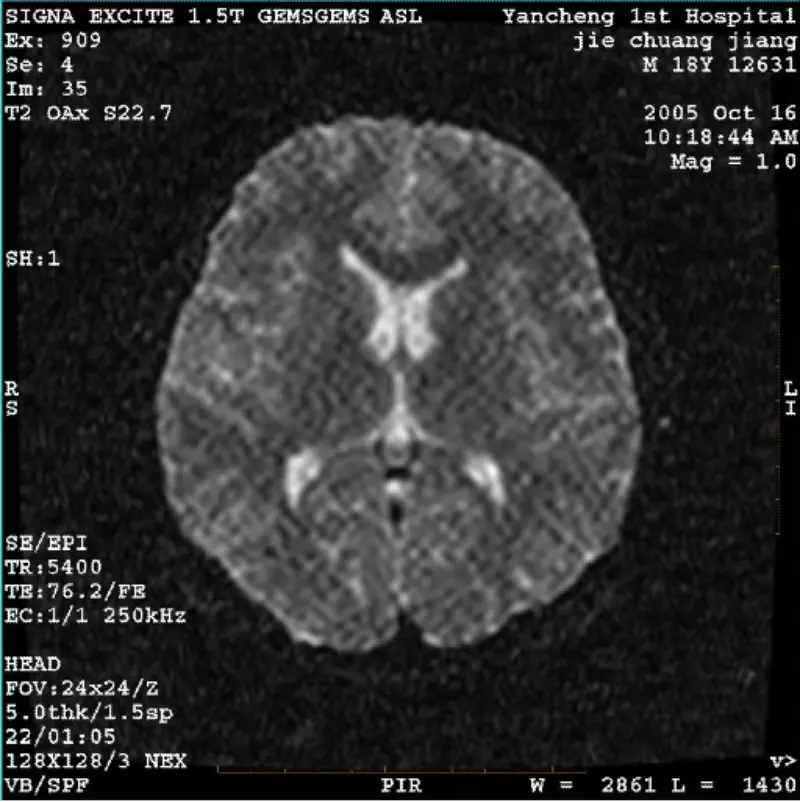

ادامه مطلبسیستم: 1.5T Signa Twin Excite II (نسخه نرم افزاری 11.0M4) مشکل/نشانه DWI (حالت زوم و حالت کل) و فیستا (حالت زوم و حالت کل) داشتن تصویر بدون توجه به استفاده از سیم پیچ بدنه یا سر، مصنوع مشبک یا مخملی قابل مشاهده است سیم پیچ، تصویر معمولی دیگر طبیعی به نظر می رسد